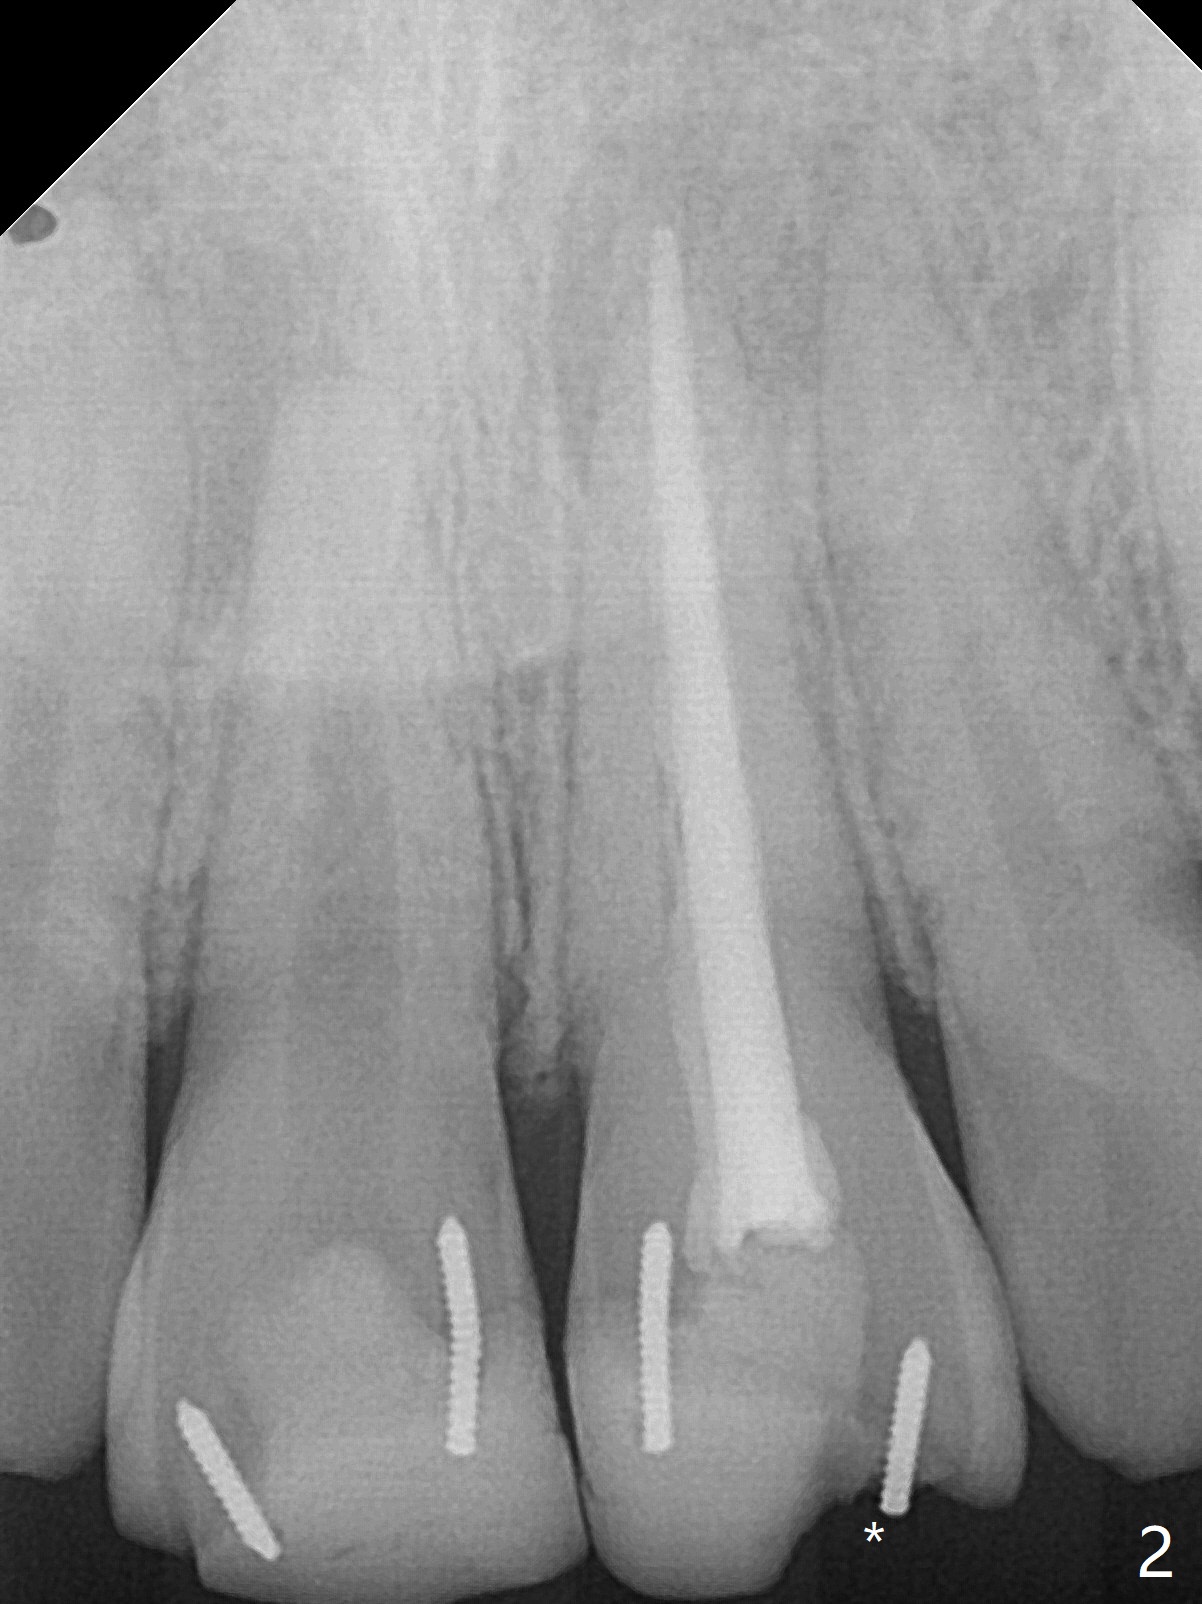

15岁男去年急诊来诊所左上1疼痛(图一:9号牙),两个中切牙8-9岁外伤,侧切牙活性测定:活髓,建议8,9 apexification。一年后(这个月)他又回来要求9号牙树脂修复(图二:*),他在马来西亚看望爸爸时,突然牙痛在那里做根管治疗。现在两个中切牙颊侧根尖都有触痛。树脂修补后,他回来做8号牙牙髓治疗,想象根管宽大,但是根尖2-3毫米根管弯曲,必须事先弯曲10号扩大针才能进入,最后扩大针是rotary file, 40/.04, 21.5毫米(图三),好像工作长度不够,仅仅增加半个毫米,使用15号扩大针,病人觉得疼痛(没用局麻药),不再扩大,保持原来根尖狭窄(可以吗?)。反复冲洗后放置氢氧化钙糊剂(图四),根管仿佛挺粗的,根尖根管还需要扩大吗?根尖片清晰度不好,看不出根尖闭锁与否,需要拍摄CT吗?需要使用MTA促进根尖关闭吗?